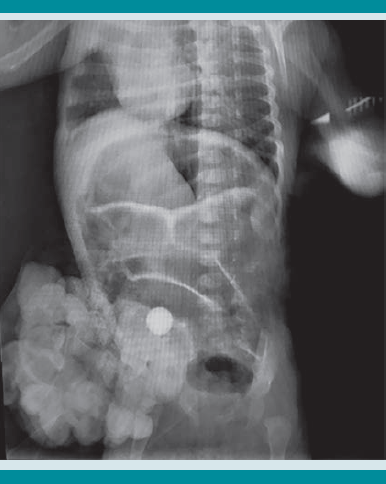

Los reportes de los exámenes de laboratorio y gasometría sin alteraciones. En las radiografías toracoabdominal antero-posterior y lateral de abdomen (Figuras 3 y 4) se observó una canica en la cavidad abdominal. Con lo anterior se estableció el diagnóstico de ruptura de saco herniario umbilical asociada con la colocación de un cuerpo extraño, con evisceración.

Se realizó intervención quirúrgica de urgencia, con plastia e introducción de las asas intestinales, sin contratiempos ni complicaciones (Figura 5 y 6). Los hallazgos quirúrgicos revelaron la existencia de un objeto extraño en la cavidad (canica) y las asas del intestino delgado evisceradas. El tamaño del defecto de la pared era de 2 cm de diámetro, a la altura del ombligo.